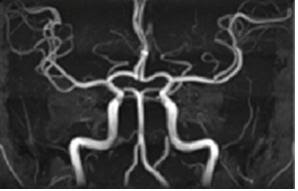

반면에 MRA는 혈관의 구조와 혈류를 시각화하는 데 집중된 기술입니다. 성공적인 심혈관 진단을 위해 혈관의 상태를 정확히 파악하는 것이 중요한데, MRA는 이러한 혈관 최적화 진단에 매우 효과적입니다. MRA는 MRI의 원리를 기반으로 하면서도, 특정한 혈관을 강조하여 더 잘 보기 위해 조영제를 사용하기도 합니다. 이로 인해, 의사는 혈관의 톤과 흐름을 보다 명확하게 관찰할 수 있으며, 협착증, 혈전, 기타 혈관 질병의 발견에 큰 도움을 줍니다. MRA와 MRI는 모두 안전한 검사 방법으로, 특히 방사선 노출이 없다는 점에서 의료진과 환자 모두에게 선호됩니다. 하지만 두 기술의 적용 분야와 사용하는 기법이 다르기 때문에 의사와 환자 모두가 각 기법의 특성을 잘 이해하고 활용하는 것이 중요합니다.

- 혈관의 협착이나 폐색을 진단: MRA는 동맥과 정맥을 자세히 시각화하여 혈관의 좁아진 부분이나 막힌 부분을 확인할 수 있게 해줍니다.

- 뇌혈관 질환 평가: 뇌졸중을 진단하기 위한 주요 진단 방식으로 활용되며, 뇌혈관의 이상을 조기에 발견할 수 있습니다.

- 동맥류 및 기타 혈관 abnormality 조기에 발견: MRA는 암 투병 과정에서 혈관의 형태를 알 수 있게 하여, 동맥류와 같은 혈관 기형의 조기 발견에 매우 효과적입니다.

MRA의 장점 중 하나는 빠르고 비침습적이라는 것입니다. 검사 시간이 짧고, 환자가 검사 중 거의 활동을 하지 않아도 된다는 점에서 많은 사람들에게 여전히 편리함을 제공합니다. 또한, MRA는 다양한 조영제와 기술을 조합하여 각기 다른 유형의 혈관을 더욱 선명하게 보여주는 데에 도움을 줄 수 있습니다. 예를 들어, 특정한 조영제를 사용하게 되면 말초혈관의적절한 진단이 가능해지며, 이는 나쁜 혈류 상태를 진단하는 데 중요한 역할을 합니다.